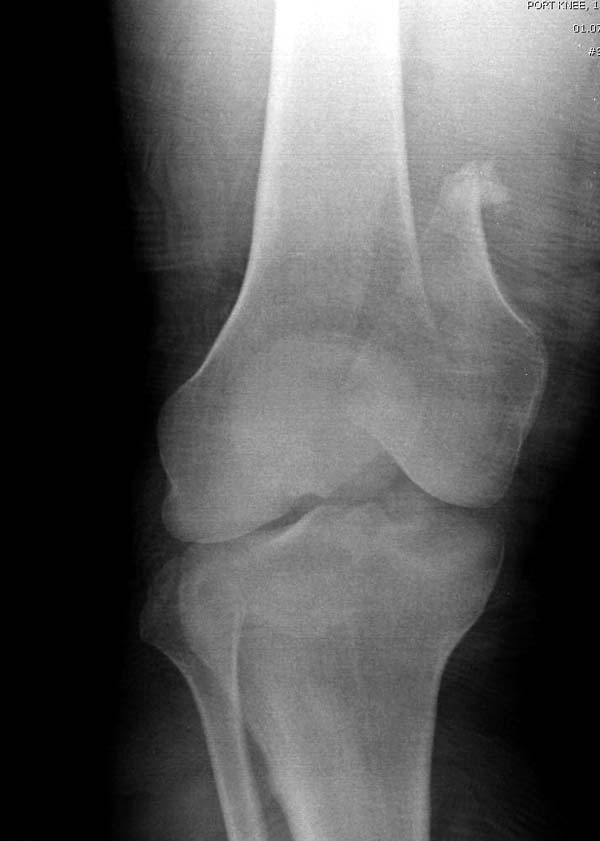

[Ortho] Нелеченный перелом Hoffa

Здесь представлены различные варианты фиксации перелома, а также снимки

комбинации перелома с повреждением хряща (12-19). Пластика хряща

OsseoFit и установка custom made plate.